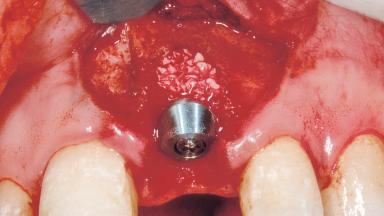

Immediate Placement of an Implant in a Maxillary Left Central Incisor Site

A 33-year-old female patient presented with an upper left central incisor that required extraction after a failed endodontic therapy. The tooth had been traumatized when the patient was a teenager and had undergone several endodontic treatments, including two apicectomy procedures. The patient was in good health and did not smoke. Clinical examination showed that the patient had a high lip line. In full smile, the gingival margins of the upper teeth were visible to the first molars. The gingival margins of central incisors 11 and 21 were only just showing. Examination of tooth 21 confirmed that the tooth was mobile and had hypererupted by 1 mm.

| Bone Augmentation | Horizontal|Simultaneous |

| Augmentation Materials | Xenogenous|Membrane |

| Placement Protocol | Immediate implant placement |

| Socket Integrity | Damage to one or more bone walls |

| Bone Volume | Damage to one or more socket walls |